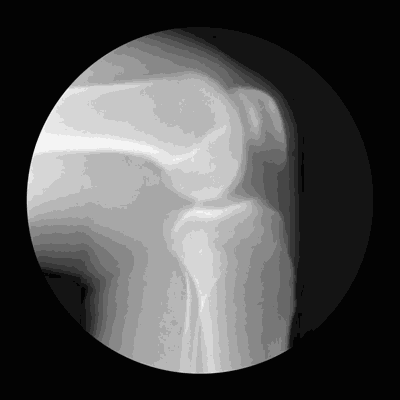

關節僵硬:它們最怕5個字

關節是骨骼之間的連接點,一旦關節出了問題,人的行動力就會受限,久之人就垮了。

1、怕老:隨著年齡的增長,人體軟骨營養缺乏,骨骼中的無機物增多,骨骼彈力與韌性減低,易導致關節軟骨和骨退行性病變。

2、怕胖:體重增加,下肢關節承重的壓力也會增加,引起體位、步態變化,改變關節的生物力學,發生膝內翻或膝外翻,也就是常說的“O”形腿或“X”形腿。

3、怕傷:在運動、出行的過程中,如果出現急性外傷,一定要及時去醫院治療,以免留下後遺症。

不及時治療或充分休息,容易留下病根,比如“習慣性崴腳”。

4、怕勤:關節用得太狠,容易導致機械磨損,破壞軟骨。

頻繁爬山、爬樓等是非常傷害關節的。建議大家平時通過慢跑、游泳鍛煉,既不損傷關節又能鍛煉。

5、怕冷:關節受涼會引起疼痛,易導致關節僵硬。